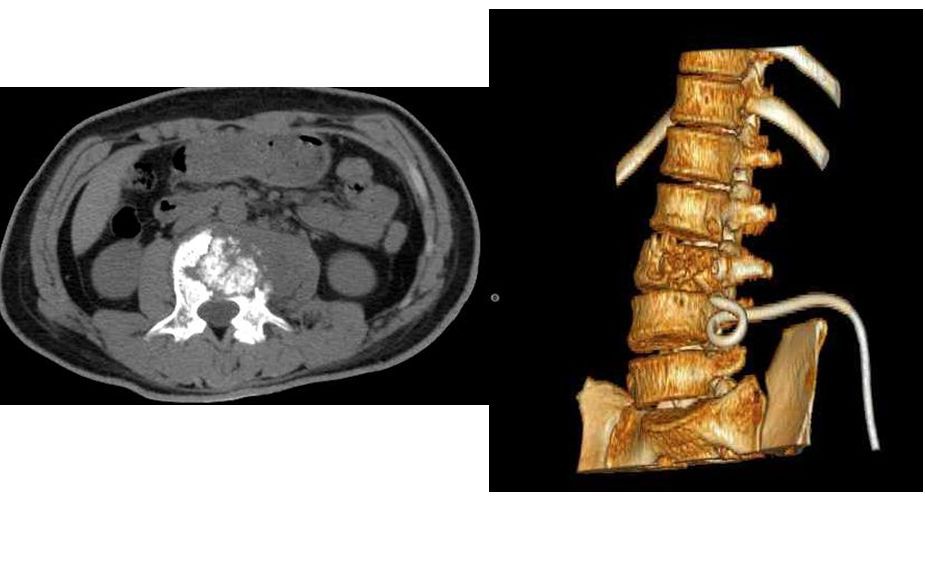

脊柱结核ct

脊柱结核ct,脊柱ct

脊柱结核骨质破坏(ct图1)脊柱结核(ct图)了解脓肿位置及大小,与周围

脊柱结核病例1:腰椎结核前路病灶清除植骨内固定术

脊柱结核的ct及mri诊断影像天地